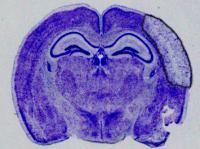

image: The researchers used a molecule called Gap19 to block the hemichannels, in the same stroke model, which resulted in smaller stroke damage. view more

Credit: University of British Columbia

For the study, the researchers used a genetic approach that mutated the channel proteins, called connexins, in such a way that blocks the formation of hemichannels. This allows the astrocytes to protect the neurons, significantly reducing the size of the stroke injury in the brain. The researchers also used a molecule called Gap19 to block the hemichannels, in the same stroke model, which also resulted in smaller stroke damage. Together, the two approaches demonstrate that connexin hemichannel blockers could be used as a neuroprotective agent in stroke.